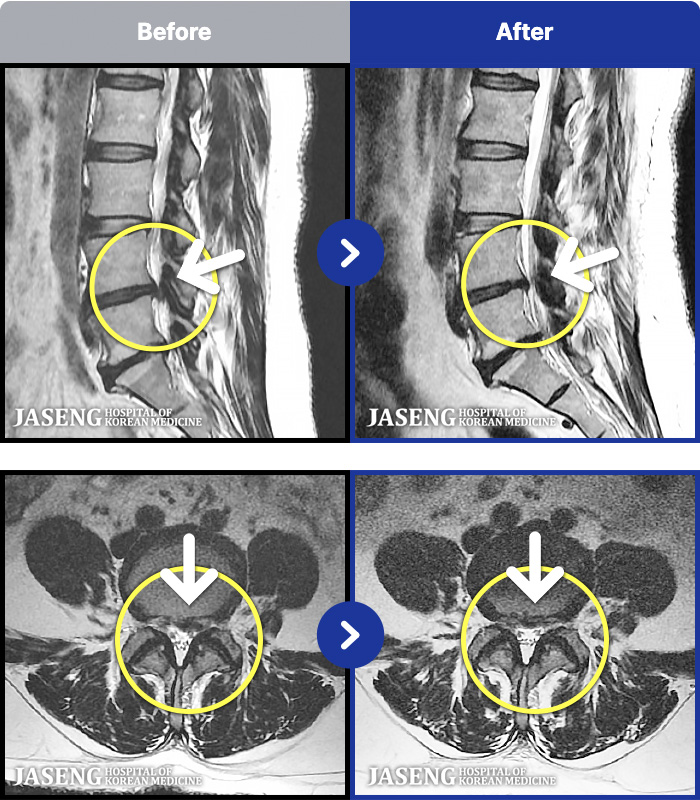

1,304 MRI ũ ʸ Ȯϼ.

[뱸] 19.11.28~25.05.06